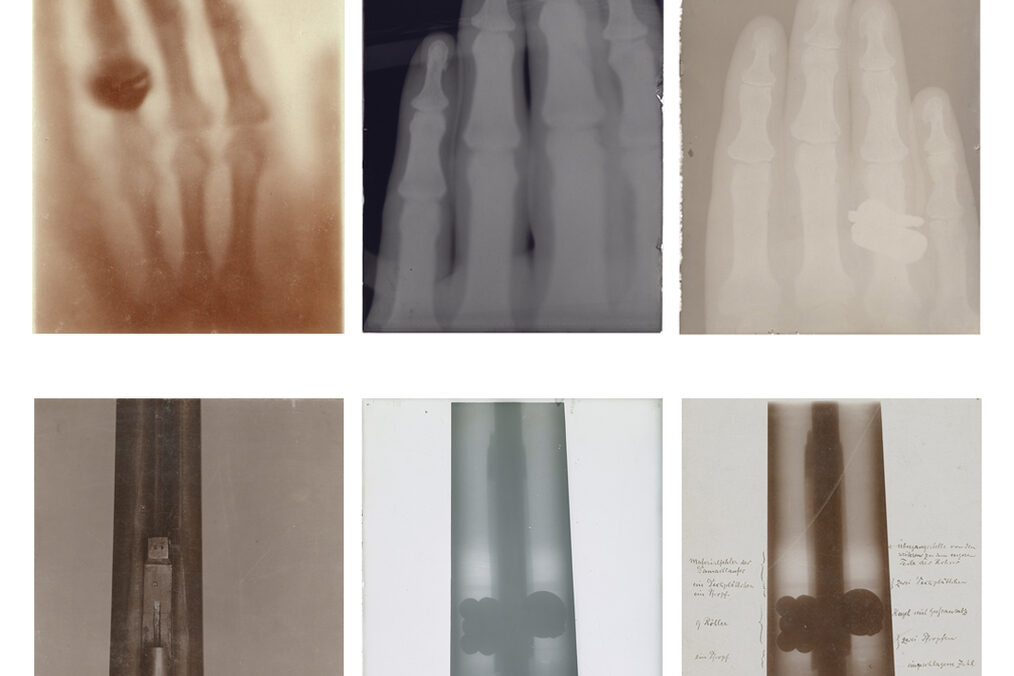

Eintrag ausgewählter Röntgenbilder von Wilhelm Conrad Röntgen aus den Archiven des Deutschen Röntgen-Museums in Remscheid-Lennep in das UNESCO Weltdokumentenerbe (Memory of the World Register)